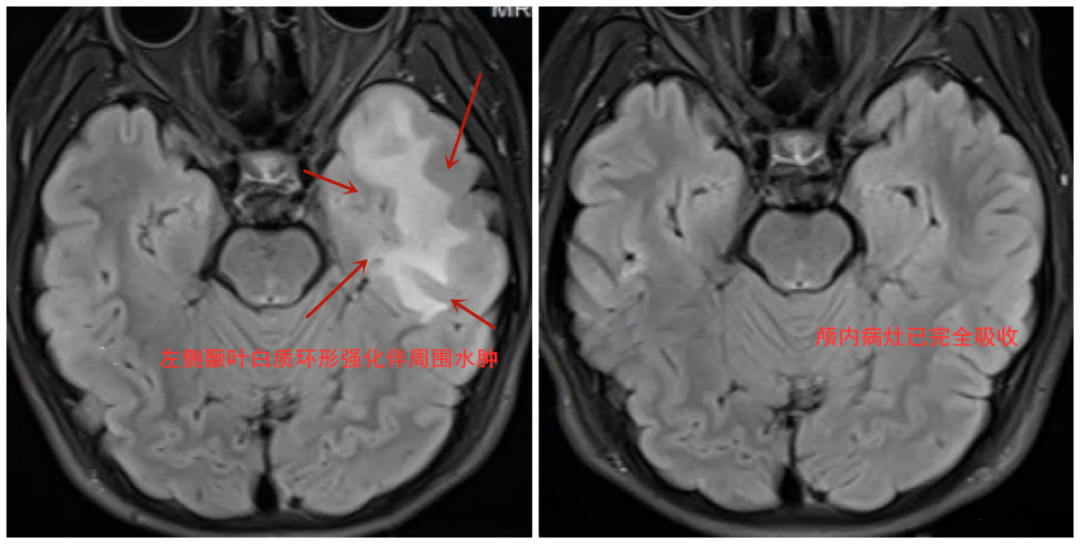

医生表示,俊俊感染弓形虫的原因,与其家中长期不及时处置猫的排泄物等行为有关。经一个月的对症驱虫治疗,11月19日,俊俊颅内的病灶已完全吸收,再未发作癫痫。

患者检查影像图片。图源:武汉晚报